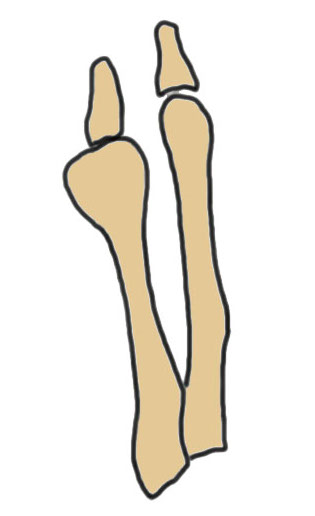

Coughlin Classification

| Type I | Type II | Type III |

|---|---|---|

| Prominent lateral condyle 5th metatarsal head | Lateral bowing of 5th metatarsal |

Increased 4/5 intermetatarsal angle Normal 5 degrees 5th metatarsal straight |

| Lateral condylectomy | Osteotomy | Osteotomy |

Lateral bowing of 5th metatarsal

Increased intermetarsal angle (IMA). Normal is 5 degrees